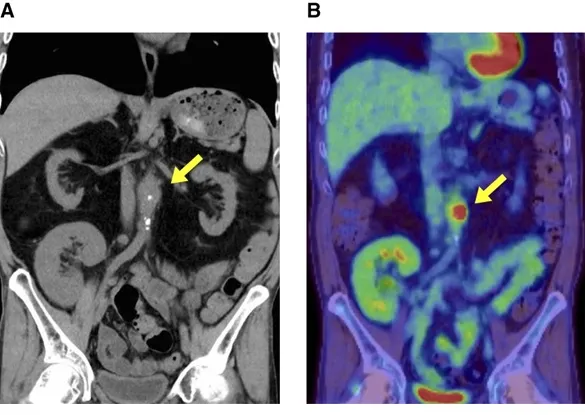

1. TC abdominal no 6º dia de investigação, sendo identificado um abaulamento focal da parede anterior da aorta abdominal com calcificação e “borramento da gordura peri-aórtica.

2. PET/CT (16º dia): Captação de FDG no mesmo local, confirmando inflamação ativa – diagnóstico: aortite infecciosa por Salmonella.

Achados de imagem na aortite infecciosa. (A) TC no 6º dia mostra abaulamento focal e calcificação da parede anterior da aorta abdominal, próxima à artéria mesentérica superior, com borramento da gordura ao redor (sinal de inflamação). (B) A PET/TC no 16º dia evidencia captação de fluorodeoxiglicose (FDG) na mesma região, indicando inflamação ativa.